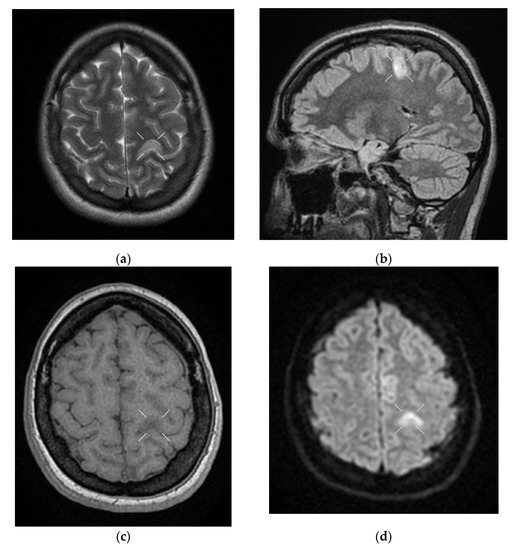

Figure 2. Cerebral native and contrast-enhanced MRI and angiography, and CT cerebral venography highlighting the sigmoid sinus and right lateral sinus thrombosis and the inferior sagittal sinus and right sinus thrombosis, associated with right temporal cortical and subcortical subacute hemorrhage, supratentorial recent subacute synchronous lacunar infarct, (cytotoxic and vasogenic) thalamic–lenticular–caudal edema, and supratentorial non-specific demyelinating lesions. Magnetic resonance imaging shows cortico-subcortical subacute hemorrhage in the right temporal lobe (a,b) T1 and T2 hyperintensities. (c) methemoglobin signal. (d) heterogeneous contrast enhancement. (e) supratentorial recent subacute lacunar infarction in a millimeter lesion in hypersignal FLAIR, restrictive in diffusion coefficient. (f,g) supratentorial recent subacute lacunar infarction located in the corpus callosum. (h,i,j,k) cytotoxic and vasogenic edema in diffuse T2 and FLAIR high signal and moderate restriction in diffusion coefficient in the left thalamus. (l,m,n,o) cytotoxic and vasogenic edema in left lenticular-caudate nucleus. (p) right sigmoid and lateral sinuses thrombosis—T1 and T2 hyperintense material, without contrast enhancement. The intravenous post-contrast and native cranio-cerebral MRI examination highlights are as follows: oval globular formations with a non-homogeneous central portion and a periphery with a methemoglobin signal, hyper-intense T1–T2, axial dimensions of 11/10 mm maximally and heterogeneous contrast outlet, along with right temporal cortical and subcortical conglomerates, with extended moderate perilesional oedema; FLAIR hyper-intense millimeter lesions, intense and homogeneous restriction in diffusion and no-contrast outlets in the semioval centers, in the corpus callosum and in the middle temporal gyrus; diffuse signal T2–FLAIR increased in the left and left lenticular–caudal thalamus, with minimum diffusion restriction and no detectable contrast outlets; a few T2–FLAIR hyper-signal millimeter outbreaks, with no diffusion restriction and no corresponding T1, located in the white matter in the periventricular hemisphere and bilateral frontal–parietal subcortical area; normal supra- and infratentorial pericerebral liquid spaces; a symmetric ventricular system, with normal dimensions; structures of the median line in normal position; orbits and orbital content without anomalies; and paranasal sinuses with normal development and pneumatization. Magnetic resonance (MR) cerebral arteriography and venography indicated the following: internal carotid arteries symmetrically disposed, with a normal trajectory and caliber; anterior cerebral arteries and normal average bilaterally detached from the internal carotid, with no areas of stenosis or circumscribed dilation, with a homogeneous intralumenal signal; vertebral arteries, basilar artery, upper cerebral arteries and communicating arteries with a normal trajectory and caliber; hyper-intense T1–T2 material, with a no-contrast outlet, which transversely occupied the sinuses and sigmoid on the right side; and a lesion with the same signal characteristics situated along the right sinus and extended towards the inferior sagittal sinus; the rest of the dural sinuses had no detectable lesions in the sequences observed.